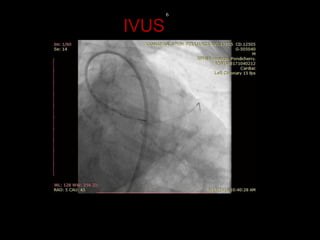

57/M ,old IWMI, CSA3

IVUS